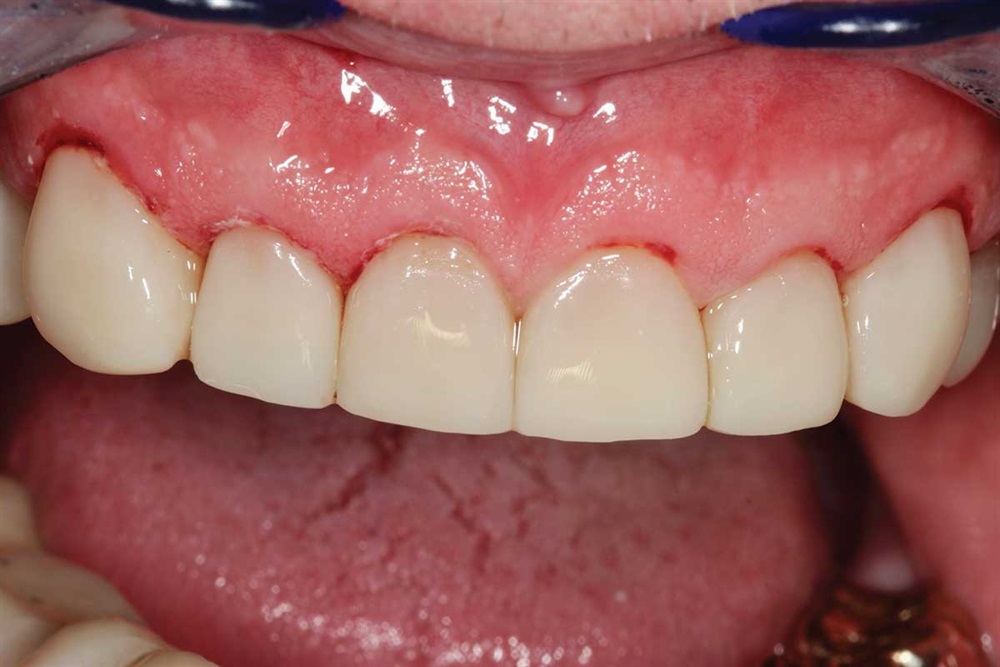

Show Your Work

Fig. 41: Occlusion being adjusted. I did not increase his vertical when I did the upper teeth.

Fig. 42: Marks show heavier contact in lateral and protrusive excursions. Again, light occlusion on the centrals because of the lack of support I was bonding to.